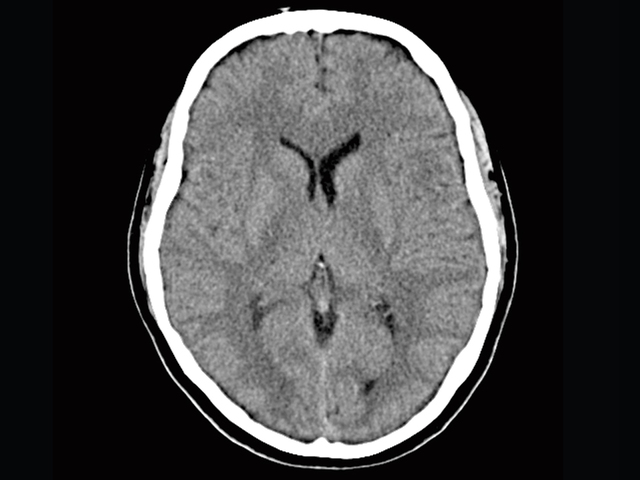

First Scan

The first scanner installation and patient brain scan was publically announced.